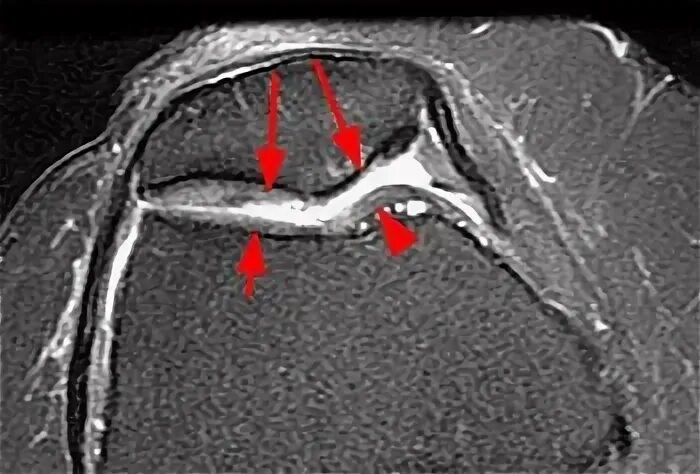

Повреждение хряща по outerbridge